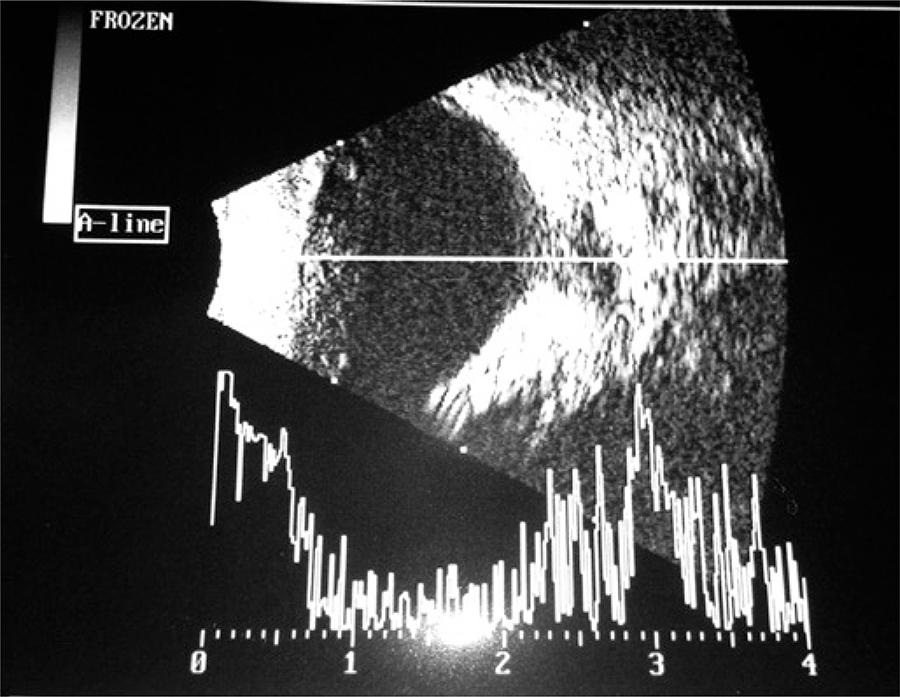

Paciente de 6 anos trazida para atendimento oftalmológico por desvio ocular (esotropia) somente em olho direito há 3 anos. Melhor acuidade visual corrigida de vultos no olho direito e 20/20 no esquerdo. Pelo método de Krimsky, apresentava esotropia de 15 dioptrias prismáticas em olho direito. Não havia alterações na biomicroscopia de ambos olhos e a fundoscopia apresentava-se normal no olho esquerdo. No olho direito, observou-se disco óptico de tamanho aumentado, recoberto por tecido glial, vasos da retina retificados e com distribuição radial. Para confirmar o diagnóstico, realizamos ecografia, que demonstrou defeito na esclera posterior típico da síndrome de Morning Glory, que consiste em aumento da escavação do disco óptico e da retina peripapilar ( e ).